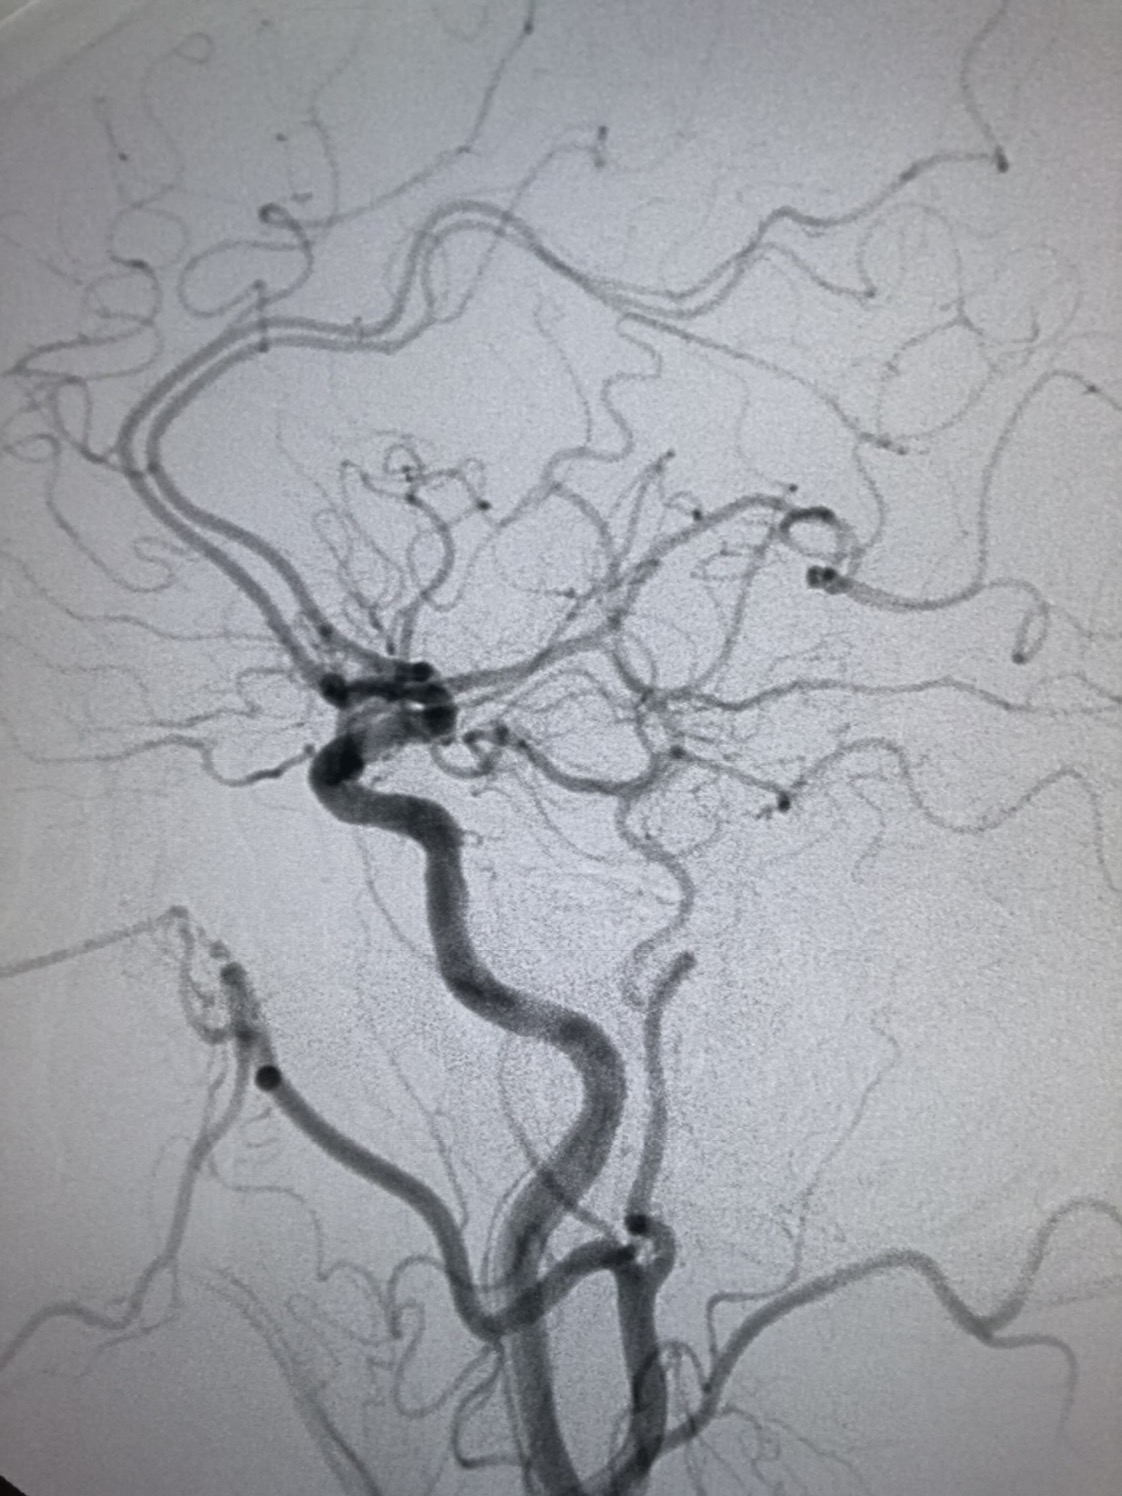

DSA:左侧颈内动脉起始部轻度狭窄。

DSA:左侧颈内动脉代偿右侧半球血供。

术后颅内血供明显改善,胚胎型大脑后动脉显影良好。